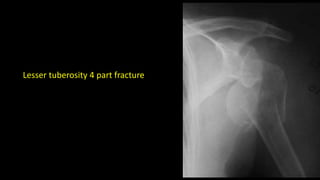

Lesser tuberosity 4 part fracture

Lesser tuberosity 4part fracture